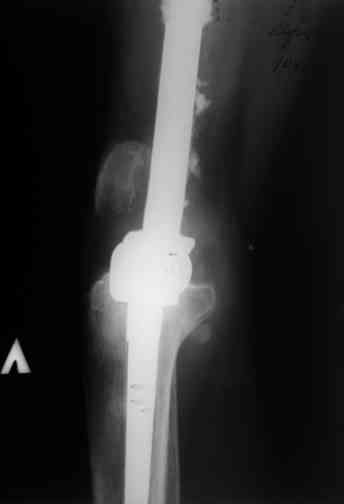

Этот стиль мне полностью приемлем и понятен. Наверно я бы поступил также. Но статистика упрямая вещь. Сколько у тебя или у другого врача опыта по замещению дефектов бедра? У меня за 25 лет работы 3, и еще около 15 случаев удлинения бедра. Случай у тебя очень сложный. Если Вы выбираете Илизаровскую методику то надо на в/з хорошую дугу, не менее 4-5 спиц с напайками.Стержни хороши когда кость не измучена и на 2-4 месяца. Здесь аппарат на 6-8 месяцев. Если есть желание я только за, и

желаю только успеха и чтоб все трудности которые будут преодолел.

Прикрепляю пример замещения дефекта бедра 20 см, после резекции по поводу опухоли, эндопротеза Сиваша, вялотекущего остеомиелита со свищами в течении 3 лет. Получилось хорошо и всего за 6 месяцев в аппарате. Колена не было. У Вас случай сложнее. Это было в 1998г. Я работал в ЦИТО и у меня было 4 больных, я занимался им с утра до ночи. Сейчас 60 больных и операций в нашем отделении 25-30 в неделю.Если могу чем помочь - нет проблем.